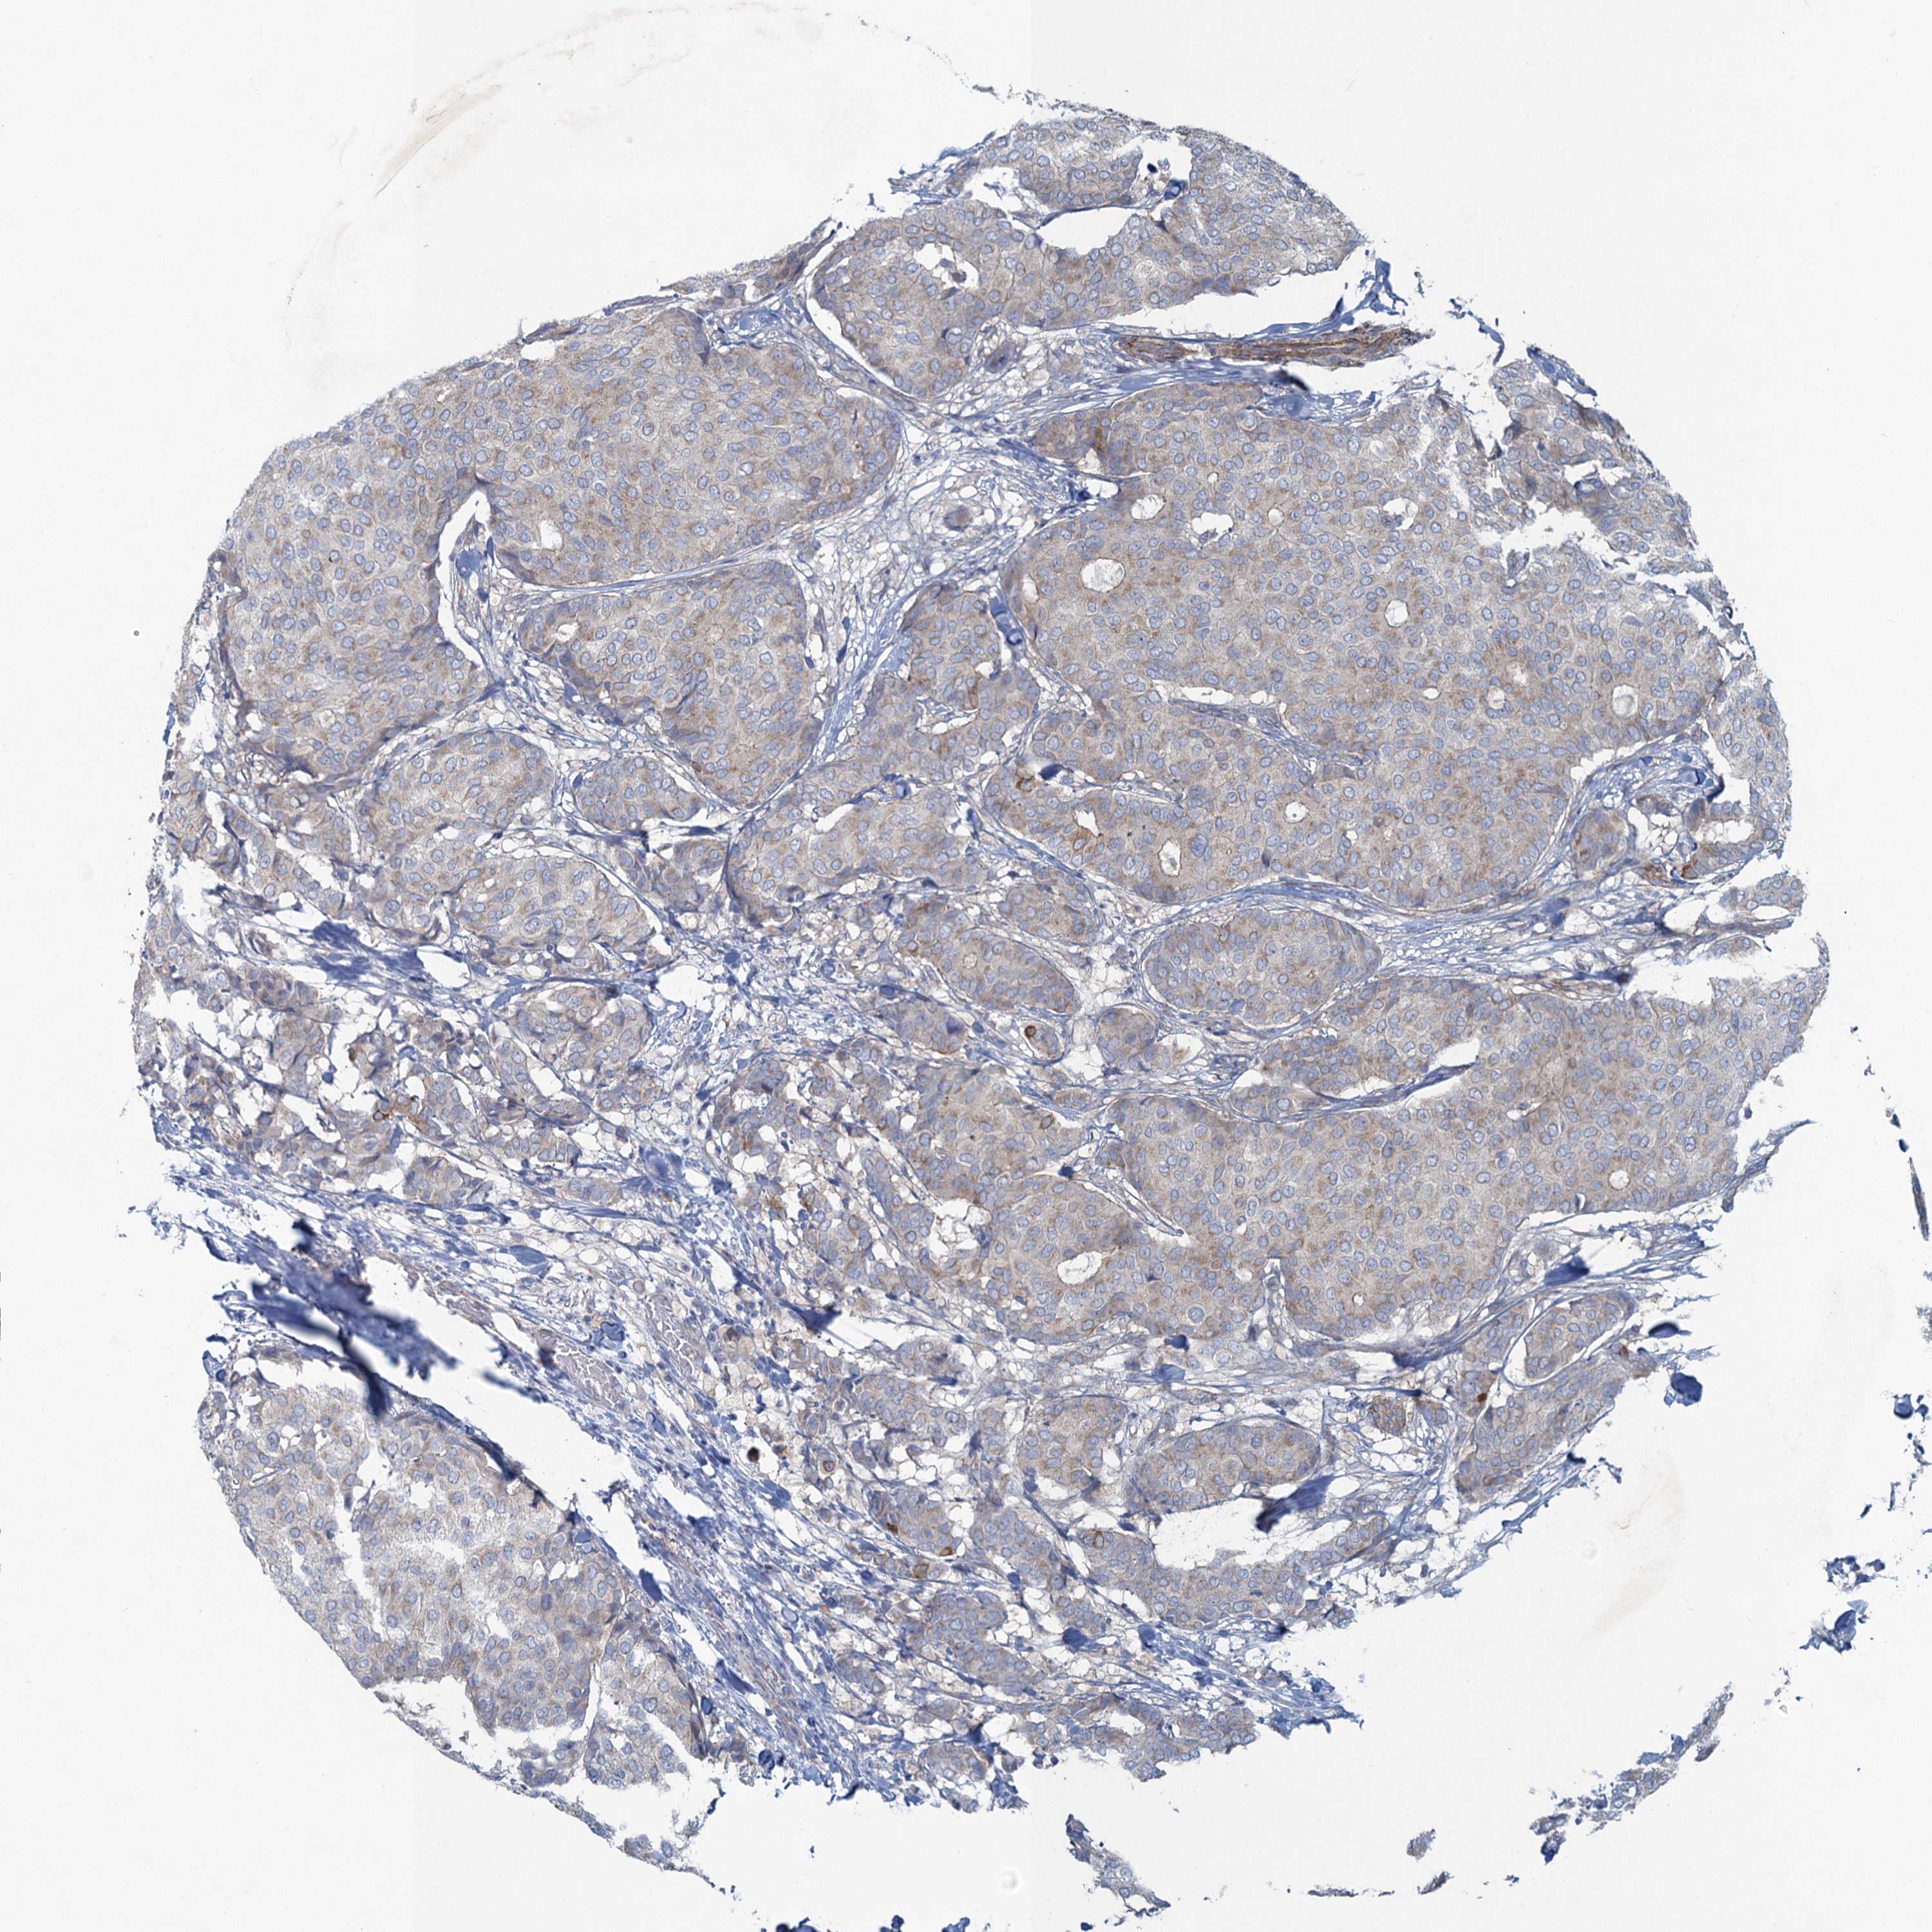

CANCER BREAST CANCER Show tissue menu

BRCA TCGA BRCA VALIDATION PROTEIN EXPRESSION